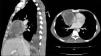

Varón de 51 años con antecedentes personales de infección por virus de la hepatitis C, exfumador, que presenta cuadro de fiebre acompañada de artralgias y pérdida de peso. Tras anamnesis y exploración física, que no aportaron ningún dato relevante, solicitamos exploraciones complementarias: hemograma, bioquímica, serologías virales, autoinmunidad, prueba de Mantoux y hemocultivos, destacando proteína C reactiva 238mg/l. Se realizaron pruebas de imagen, observando en la radiografía de tórax, imagen de densidad agua hiliar derecha y en tomografía axial computarizada (TAC) torácica, tumoración mediastínica anterior de 9×7cm, compatible con remanente embriológico infectado (fig. 1). El paciente fue diagnosticado de quiste pleuropericárdico infectado, y se inició tratamiento con antibioterapia, teniendo buena evolución, por lo que fue dado de alta domiciliaria en espera de cita para extracción quirúrgica del quiste.